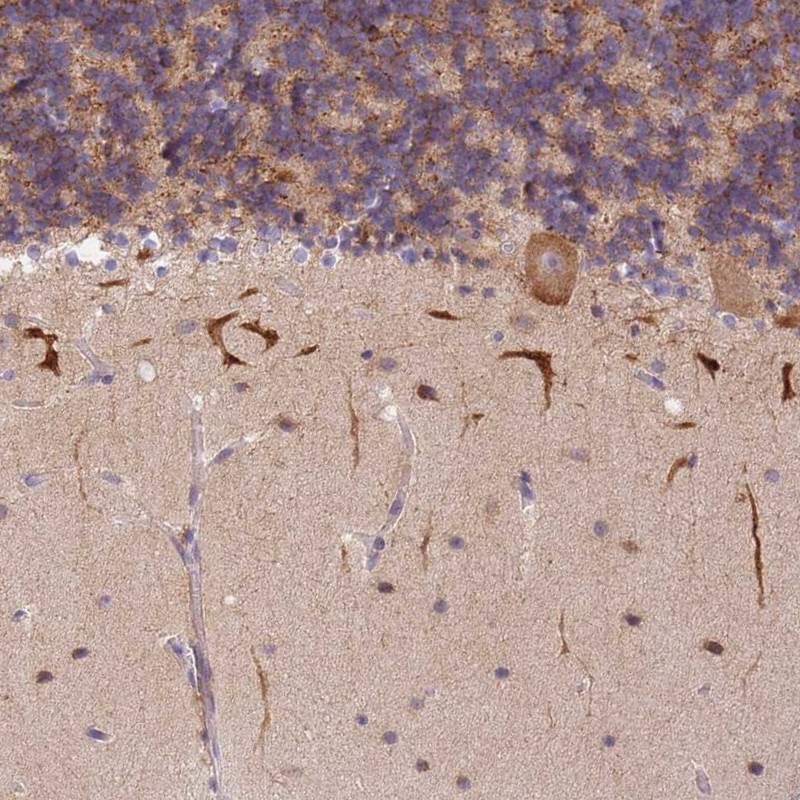

Immunohistochemical staining of human cerebellum shows moderate cytoplasmic positivity in Purkinje cells.